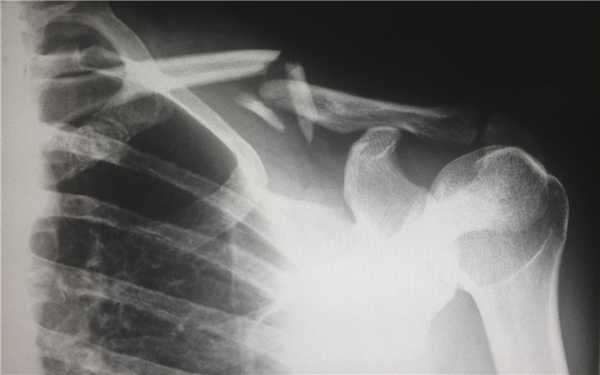

(Слева) На передне-задней рентгенограмме локтевого сустава определяется едва заметный перелом суставной поверхности головки лучевой кости без смещения. Переломы со смещением (Справа) На косой рентгенограмме локтевого сустава определяется перелом головки лучевой кости со смещением на 4 мм и угловым отклонением. Переломы со смещением >2 мм, захватывающие больший объем головки лучевой кости, или с угловым отклонением классифицируются как повреждения II типа. (Слева) На сагиттальной КТ с реформатированием через лучезапястный сустав можно видеть раздробление головки лучевой кости, соответствующее картине перелома III типа.

(Справа) На поверхностной 3D КТ с реформатированием у этого же пациента определяется вдавление и раздробление головки лучевой кости. Хотя такие реконструкции часто не дают дополнительных преимуществ оценивающему рентгенологу, хирурги-ортопеды находят их полезными при планировании операции. (Слева) На передне-задней рентгенограмме определяется заднебоковой вывих локтевого и лучеголовчатого сустава. Имеется перелом головки лучевой кости со смещением. Это повреждение III типа.